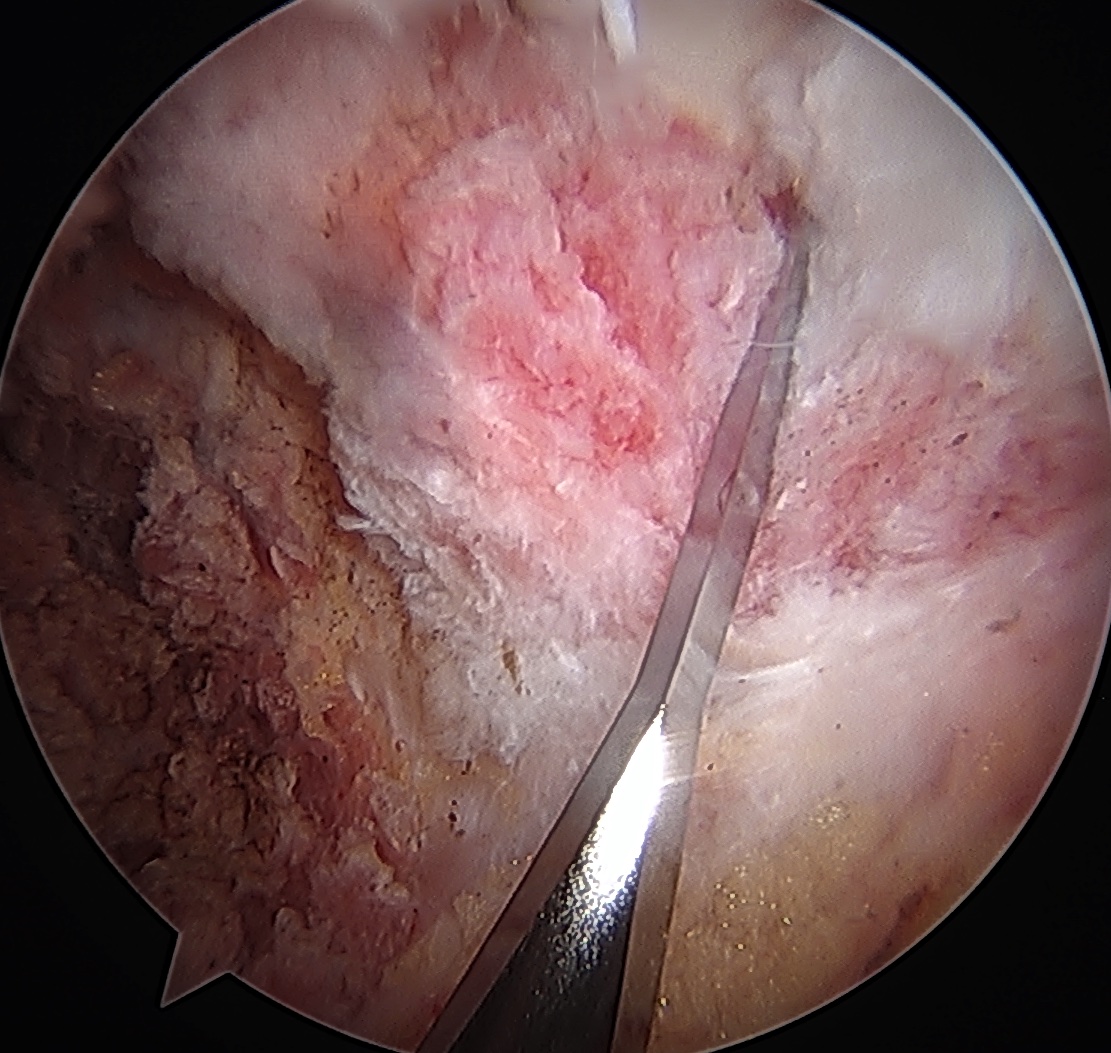

Acetabular rim trim / Acetabuloplasty

Pincer resection

Os acetabuli resection

Expose acetabulum

- place proximal capsule suspension sutures

- elevate and protect proximal capsule for later repair

- use cautery to expose acetabulum while not injuring labrum